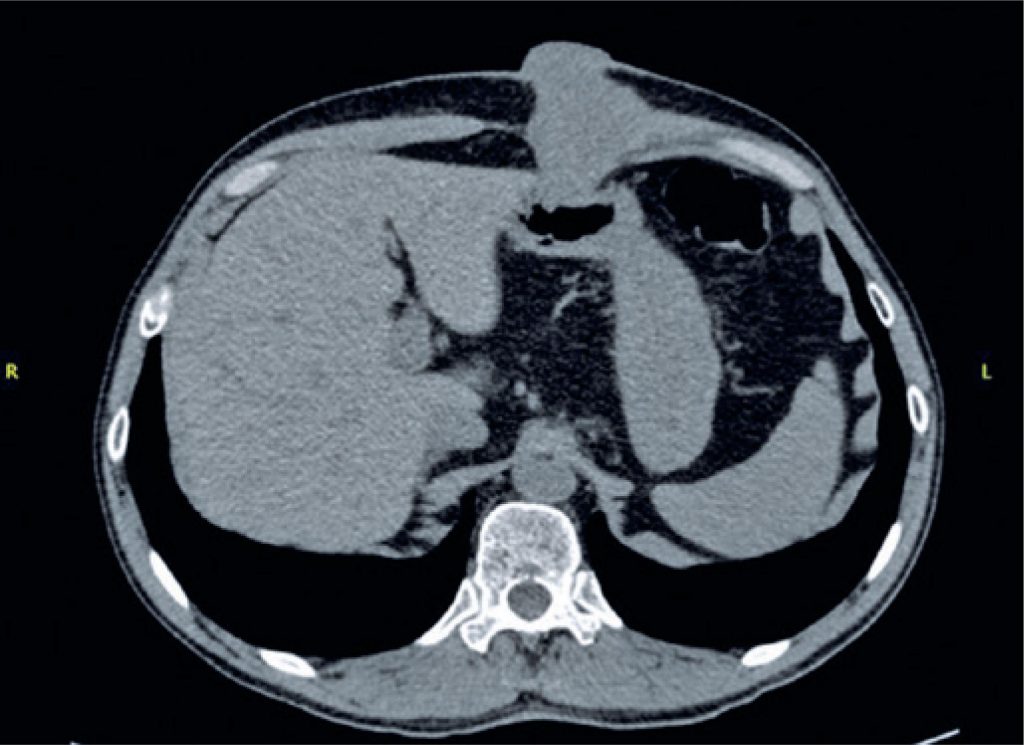

Percutaneous endoscopic gastrostomy is used to provide enteral nutritional support for patients with obstructive oropharyngeal or esophageal neoplasms. The placement of the catheter is considered safe, with few complications. Despite this, a specific complication that is considered rare, has been increasingly described in the literature, i.e., metastasis of head and neck cancer in the gastrostomy stoma. In this report, we described a case of metastasis of squamous cell carcinoma of the larynx in the gastrostomy site, and discussed the possible etiologies and alternatives, seeking to reduce the incidence of this complication.